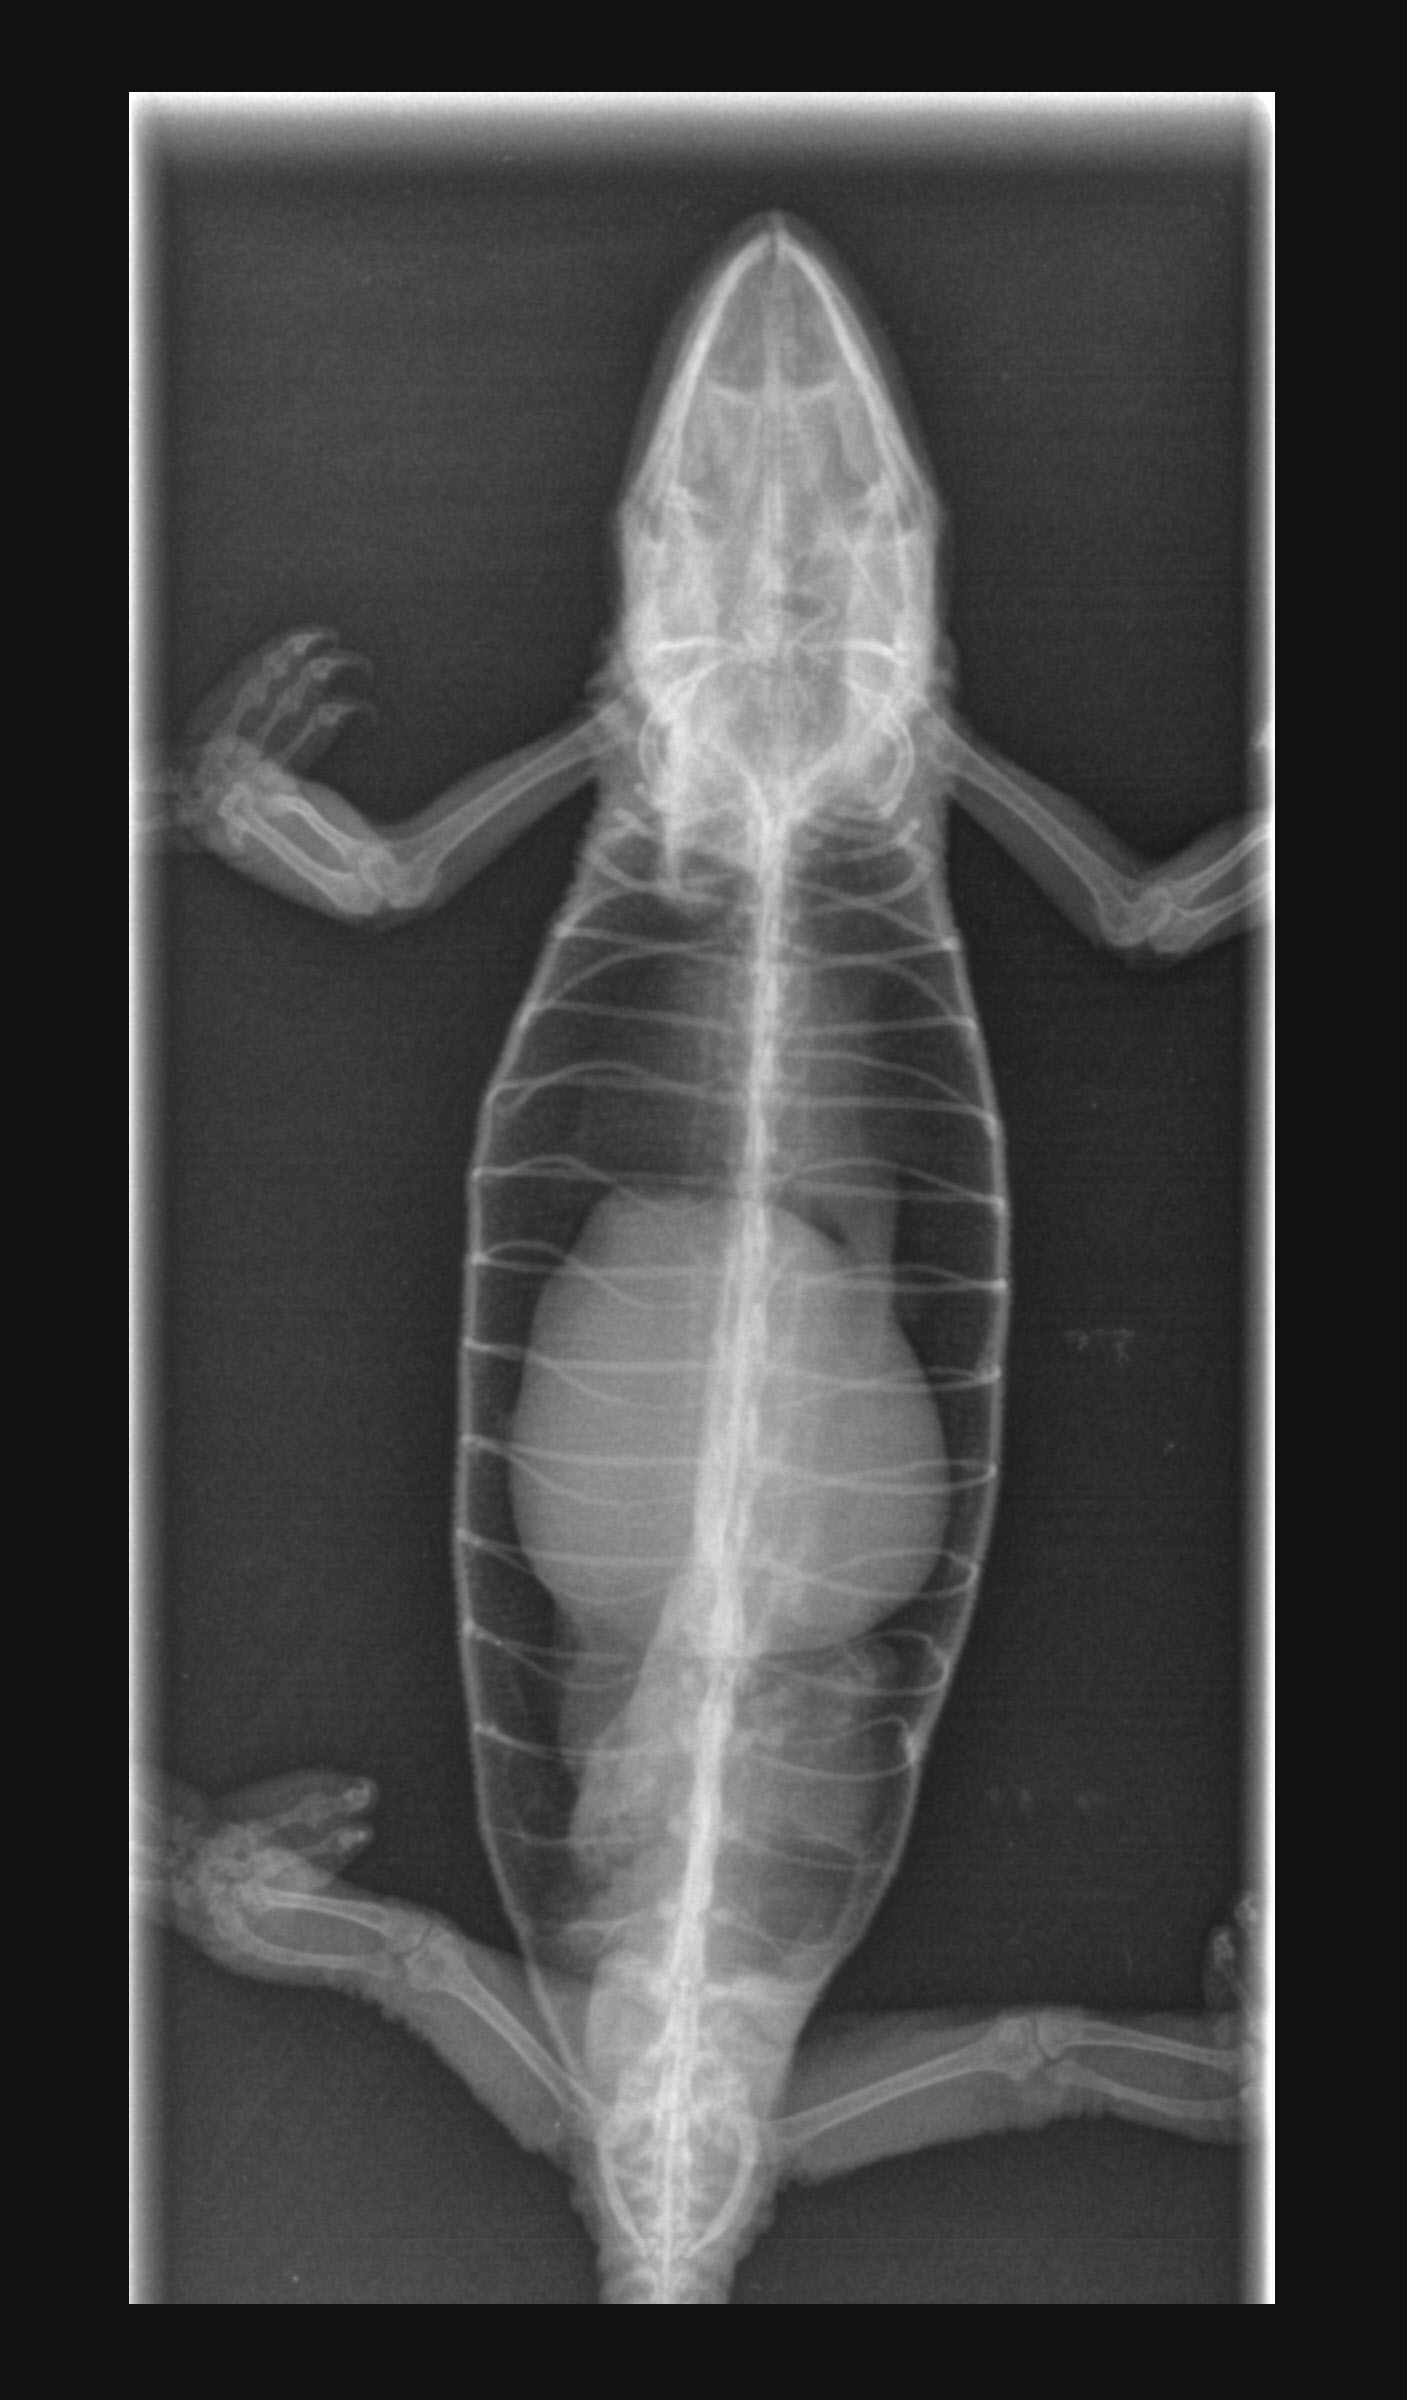

• Diagnostika, proč nepřijímá potravu, probíhala komplexním vyšetřením - od palpace, přes RTG vyšetření a ultrazvuk.

Image